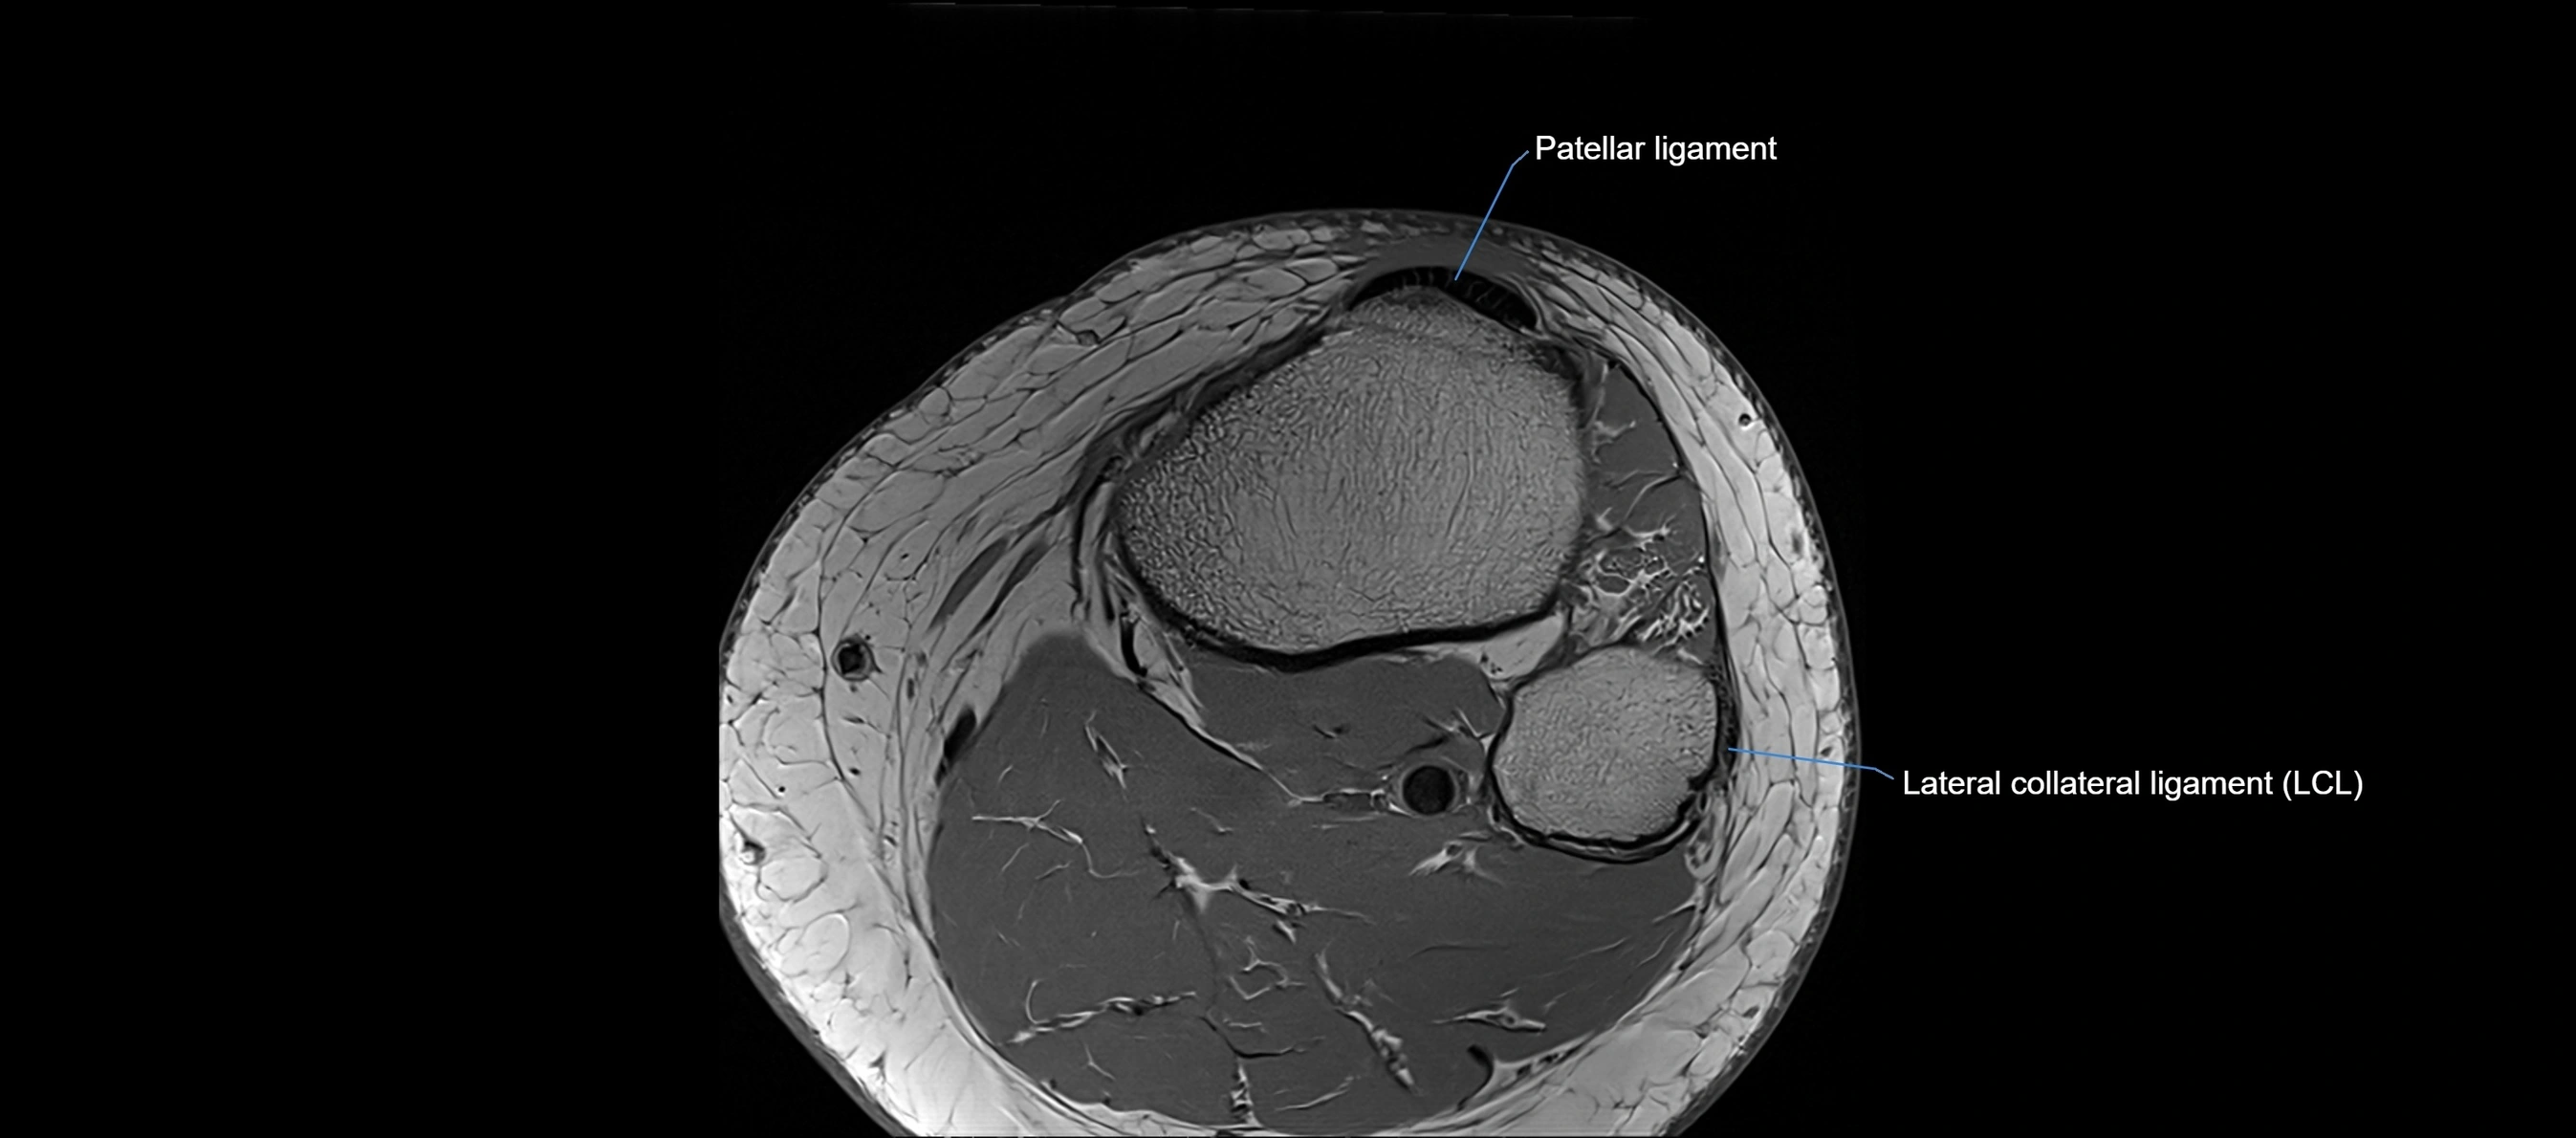

MRI images

image